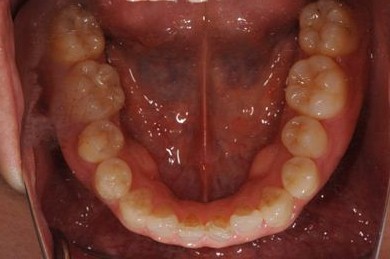

治療前

• 治療前